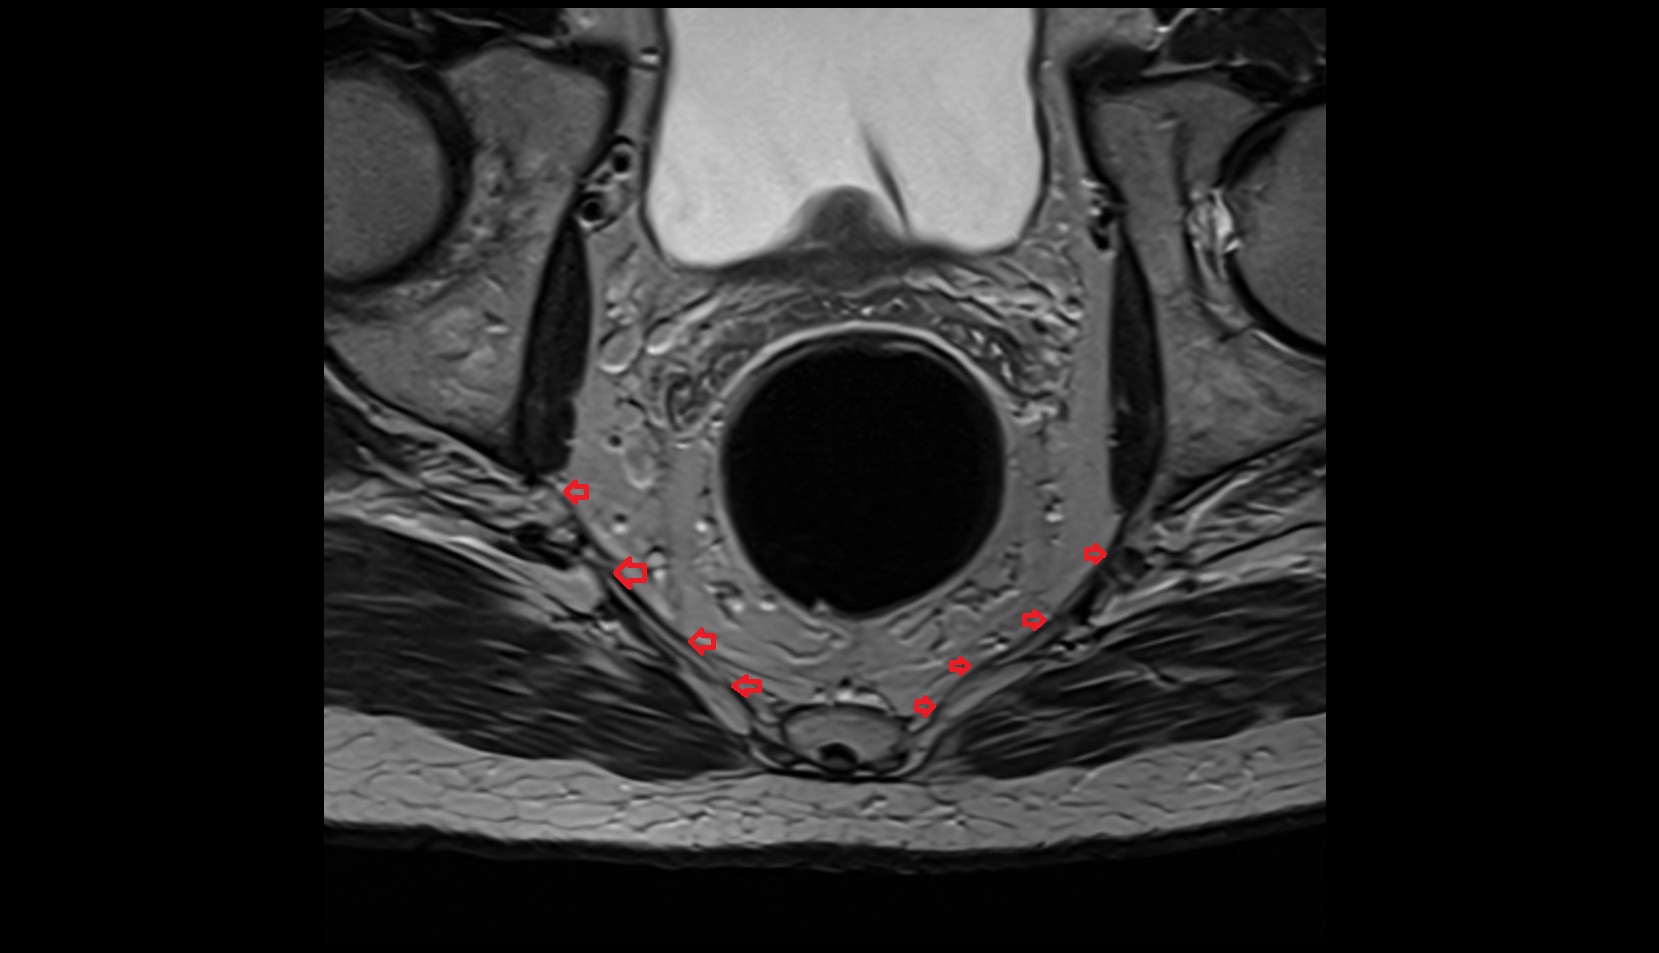

- Peripheral zone of prostate

- Anterior Fibromuscular Stroma of prostate

- Central zone of prostate

- Transitional zone of prostate